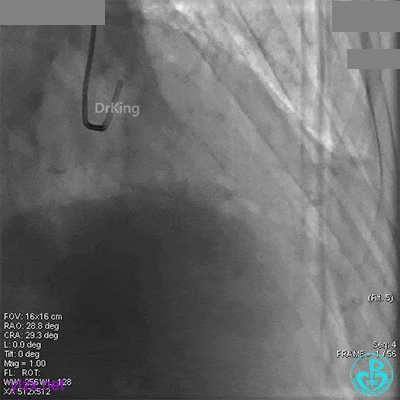

XB 3.0指引导管到位,导丝通过闭塞段至回旋支远段。

另一导丝保护分支,1.5×15mm球囊扩张闭塞处后造影,前向血流缓慢,远端分支血管没有充分显影。

1.5×15mm球囊扩张后前向血流缓慢的原因要高度怀疑慢血流。